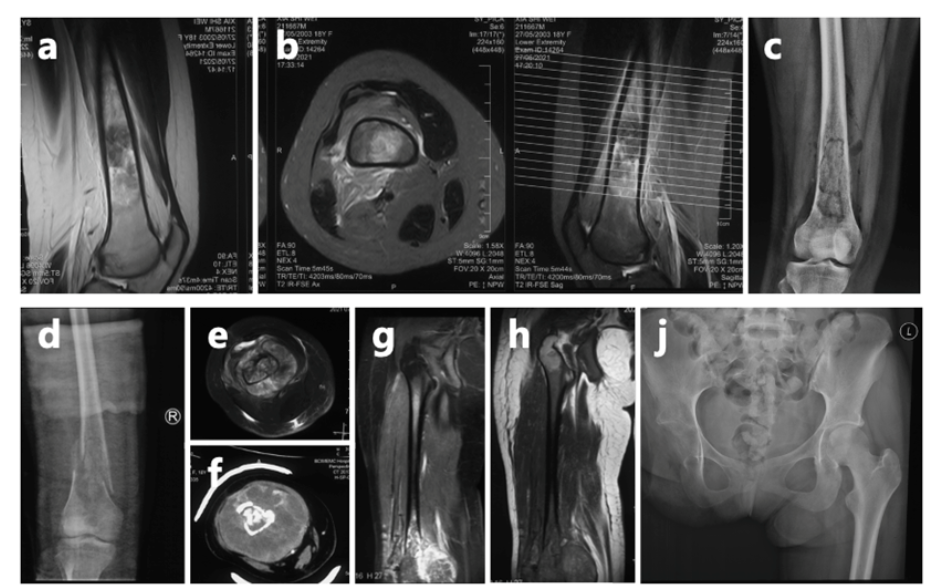

上海市第一人民医院骨肿瘤科曾讲述过夏夏的经历:她确诊骨肉瘤后经历了6次手术和无数次挑战,自2023年8月接诊以来,又完成了10次化疗和2次手术。医护人员回忆,第一次见到夏夏,她戴着假肢,拄着拐杖,拉着一个与她身高差不多的行李箱,独自走进医院。这一幕让人既心疼又敬佩。

市一骨肿瘤科介绍,对于夏夏来说,此前的截肢是一个相对可靠的选择。由于肿瘤已推挤下肢的血管和神经,并累及髋关节,截肢手术能够降低肿瘤复发的几率。然而,截肢会导致术后肢体功能的永久性丧失,对患者心理和生活质量可能造成一定影响。尽管困难重重,她始终以微笑和坚韧面对一切。

夏夏前期接受了术前化疗、截肢手术及术后化疗,使用的是一线化疗方案。然而,结疗不到一年,肺部出现转移病灶,这种情况是恶性肿瘤的普遍特性,骨肉瘤患者中并不少见,尤其是结疗后2年内,是转移和复发的高发期。

为帮助她巩固疗效并延长无病生存期,2024年2月,夏夏经过手术切除后未再进行化疗。术后5个月,左肺再次发现新发转移病灶。2024年11月,夏夏接受胸腔镜下右肺下叶切除术。2025年1月复查:右肺术后改变好转。